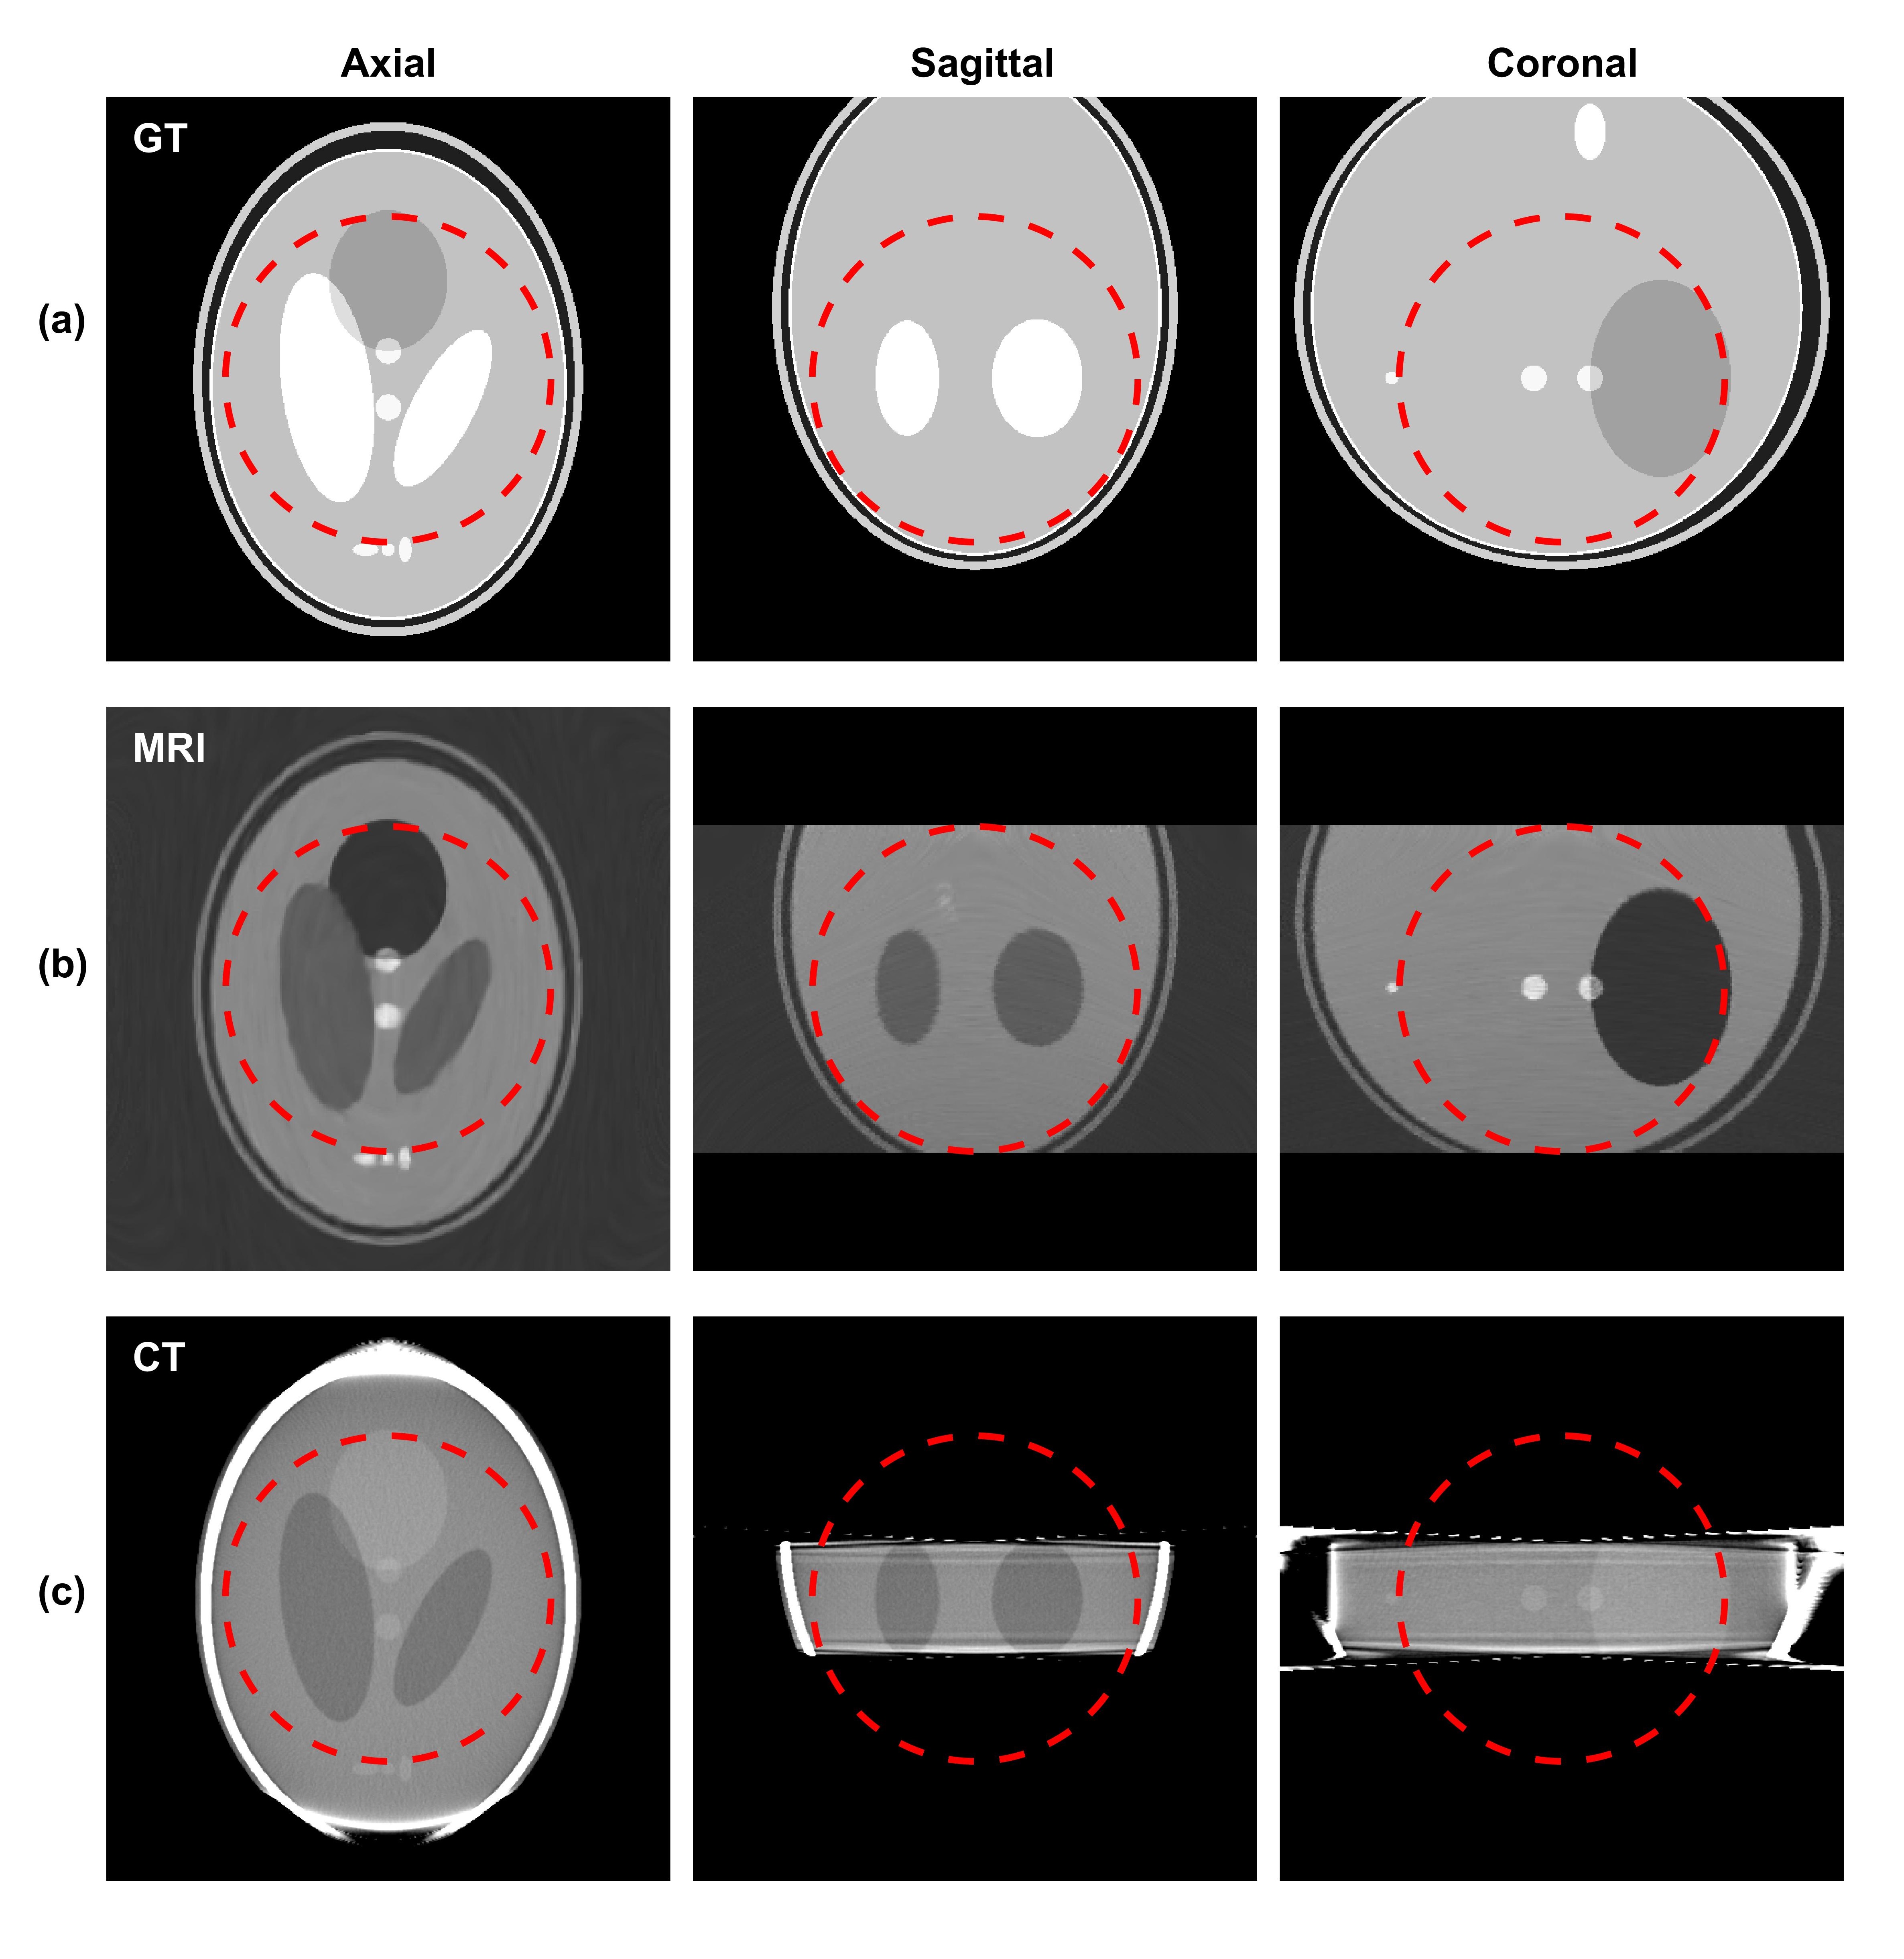

Figure 3: Orthogonal views of (a) the proton density of the 3D Shepp-logan phantom, (b) simulated MR images (TR=1,000 ms,TE=80 ms, and NEX=16), and (c) simulated CT images. The dashed red circles indicate the targeted MR FOV of 15 cm in diameter.

We first present simulation results for the Shepp-Logan phantom in Figure 3. For the MR simulation, the relaxation time TR and TE are 1,000 ms and 80 ms, respectively. The slice thickness is chosen as 4mm, and the voxel size on the axial planes is 1×1111\times 1 mm2. To reduce noise, we repeated data acquisition with the number of excitations (NEX) being set to 16. The images in Figure 3(a) display proton density of the phantom in three orthogonal views to show the structure of the phantom. Figure 3(b) shows the resulting MR image. The CT simulation results of the Shepp-Logan phantom are in Figure 3(c). The image voxel size is 0.50.50.5 mm3. Due to the narrow x-ray beam through the gap between the two magnet rings, the longitudinal coverage of the CT scan is 5similar-toabsent5\sim 5 cm.

To illustrate the performance of the proposed system with more clinical relevance, we present in Figure 6-8 results for different body sites using the VHP data. In the brain case shown in Figure 6, we remark that the relatively low resolution along superior-inferior direction in the MR image is intrinsically caused by the phantom itself. In fact, in the VHP MR image dataset the slides spacing is 3 mm, which limited the image resolution in the simulation results.

Figure 6: Orthogonal views of (a) the spin density of the VHP brain phantom, (b) simulated MR images (TR=1,000 ms,TE=80 ms, and NEX=16), and (c) simulated CT images. The dashed red circles indicate the MR FOV of 15 cm in diameter.